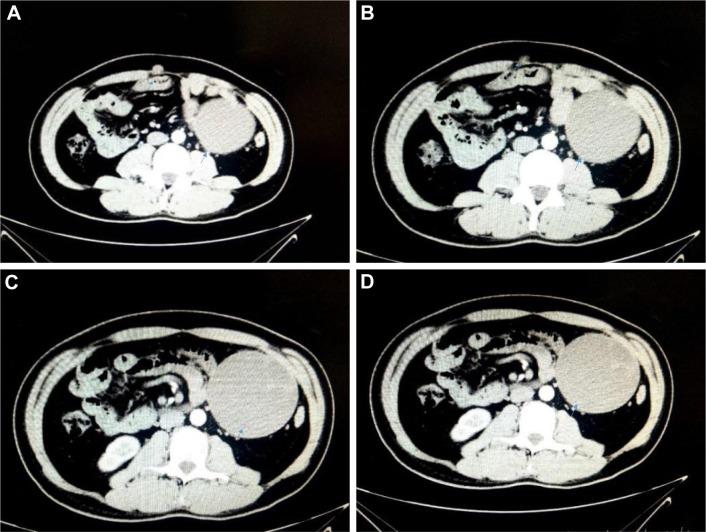

A 38-year-old man was admitted due to anterior abdominal wall nodule for 1 month. The nodule and intraperitoneal mass were resected and diagnosed IADSRCT. The patient received six cycles of adjuvant chemotherapy and his CT scan revealed metastasis in the right inguinal lymph node and omental lymph node. Anlotinib was then recommended. Anlotinib significantly reduced the lymph nodes after four cycles. The patient continued to use anlotinib as maintenance therapy, and the patient was in good condition. The side effects of anlotinib were high triglycerides and fatigue. However, its toxicity was controllable and tolerable.

一名38岁男性因前腹壁结节1个月入院。切除结节及腹腔肿物后诊断为IADSRCT。患者接受了六个周期的辅助化疗,其CT扫描显示右腹股沟淋巴结和网膜淋巴结转移。随后推荐使用安罗替尼。四个周期后,安罗替尼使淋巴结明显缩小。患者继续使用安罗替尼作为维持治疗,状况良好。安罗替尼的副作用为高甘油三酯和疲劳。然而,其毒性是可控且可耐受的。